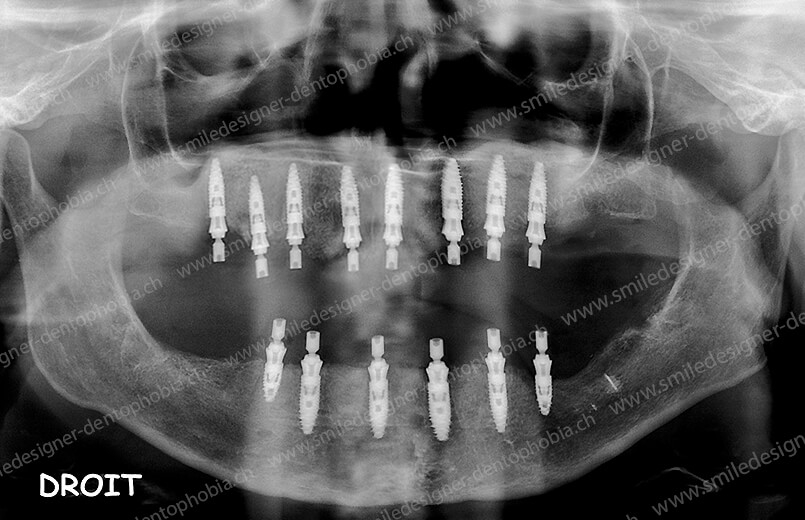

- Première étape : pose de 6 implants au maxillaire et 6 à 8 implants à la mandibule dans la zone antérieure, pour restaurer immédiatement l’esthétique du sourire.

- Deuxième étape : une série de greffes osseuses (sinus lift, greffes d’apposition, etc.) pour reconstruire les secteurs postérieurs, en attendant la cicatrisation entre chaque intervention.

- Résultat final : une arcade dentaire complète, de molaire à molaire, avec des bridges en céramique, pour une mastication optimale et un sourire naturel.